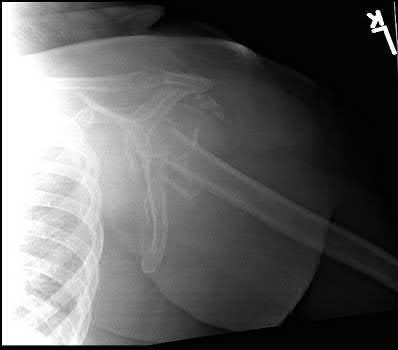

A 72-year-old woman falls down stairs and sustains the injury shown in Figure A. Additional radiographs are performed in Figure B to help assess the fracture pattern. These additional radiographs represent which of the following?

Additional traction radiographs are performed in distal humerus fractures to better understand the fracture configuration.

Traction radiographs help align the fracture fragments for better visualization. This is useful in comminuted fractures where distal fragments are telescoped or flexed on the proximal fragments, making CT scan visualization difficult.

Proper visualization can help determine (1) the approach to the distal humerus, (2) whether to perform ORIF or total elbow arthroplasty (in select patients), (3) whether to add a 3rd plate (lateral column), (4) whether to add tricortical bone graft to augment distal fixation and restore trochlear width.

Doornberg et al. examined whether 3D CT improved fracture characterization. They found that 3D CT improved interobserver and intraobserver reliability for fracture characterization and classification. It also improved intraobserver accuracy for fracture characteristics, but not interobserver accuracy. They concluded that 3D CT is helpful for preoperative planning.

Galano et al. reviewed treatment strategies for bicolumnar distal humerus fractures. They state that 3D CT compensates for oblique scans from formatting in an incorrect plane, and allows for subtraction of the radius/ulna to properly demonstrate articular incongruity, degree of comminution and column involvement.

Figures A and B show a distal humerus fracture without traction (A) and with traction (B) applied. Illustration A shows the same fracture after bicolumnar plating. Illustration B shows the different surgical approaches to the distal humerus (A, Campbell triceps splitting; B, O'Driscoll triceps reflecting anconeus pedicle [TRAP]; C, Bryan-Morrey triceps reflecting; D, olecranon osteotomy)

Incorrect Answers:

Answer 1: These radiographs aren't oblique images.

Answer 2: Radiographs under anesthesia do not add further information unless traction is applied.

Answers 4 and 5: Flexion and extension will further impact and displaced fragments and will not improve alignment.